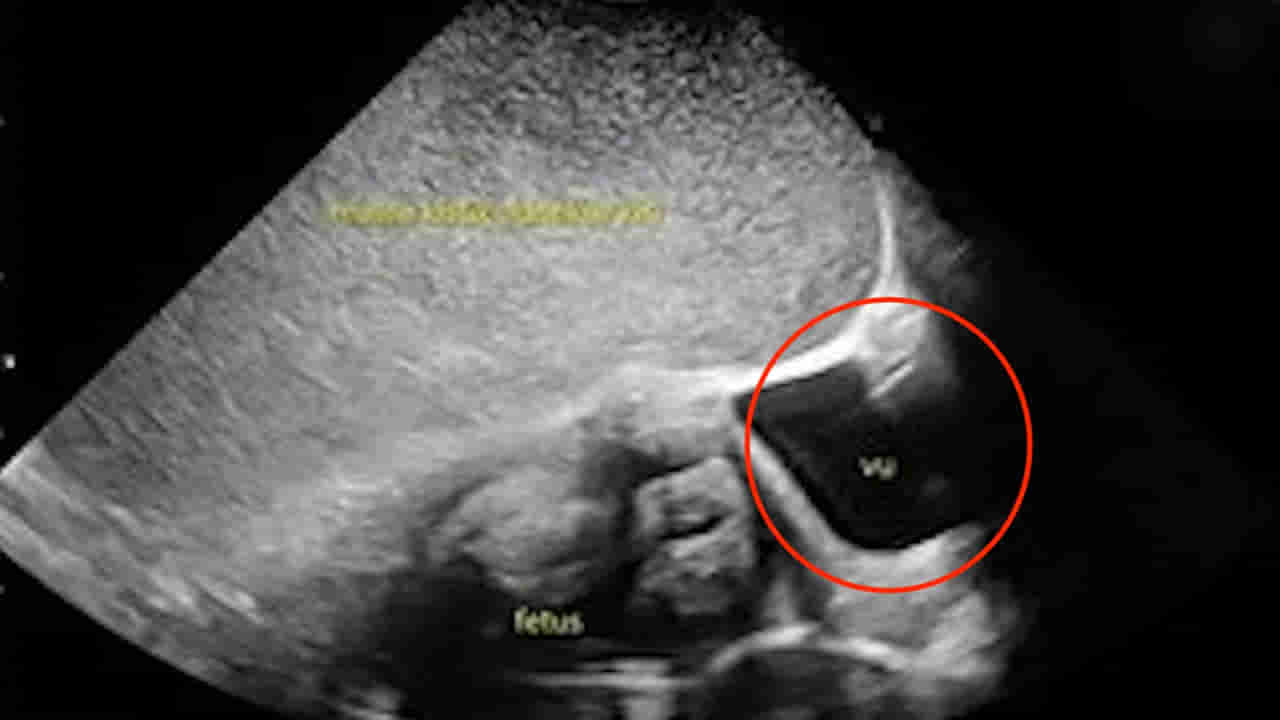

ఆమెకు ఆరు వారాల క్రితం అల్ట్రాసౌండ్ స్కాన్ జరిగింది. అందులో అండాశయ తిత్తి ఉన్నట్లు గుర్తించారు. అది ఆమెకు 18వ వారంలో మాత్రమే కనబడింది. గర్భాశయంలోని ఒక భాగంలో పిండం పెరుగుతుండగా.. ఇంకో భాగాన్ని ఈ భారీ తిత్తి కప్పేసినట్టు డాక్టర్లు కనుగొన్నారు. అంతేకాకుండా దీని వల్ల శిశువు పెరుగుదల క్షీణించడం ప్రారంభమైందని వైద్యులు తేల్చారు. సరిగ్గా ఆమె ఆస్పత్రిలో అడ్మిట్ అయిన మూడు రోజులకు వైద్యులు శస్త్రచికిత్స నిర్వహించాడు. మొదటిగా 5 పౌండ్ల బరువున్న శిశువును ఎలాంటి ఇబ్బంది లేకుండా బయటకు తీయగా.. ఆ తర్వాత ఎడమ అండాశయాన్ని కప్పేసిన ఆ తిత్తిని తొలగించారు డాక్టర్లు. అందులో నుంచి 11 లీటర్ల ద్రవం వచ్చినట్టు తెలుస్తోంది. అలాగే ఇది 35 సెం.మీ వ్యాసం కలిగి ఉంది. ఇండోనేషియాలోని జకార్తాలో ఉన్న డాక్టర్ సిప్టో మంగున్కుసుమో ఆసుపత్రిలో చికిత్స పొందిన తల్లి ఆశ్చర్యకరంగా.. త్వరగా కోలుకుంది. ఎలాంటి సమస్యలు లేకుండా డిశ్చార్జ్ అయింది.